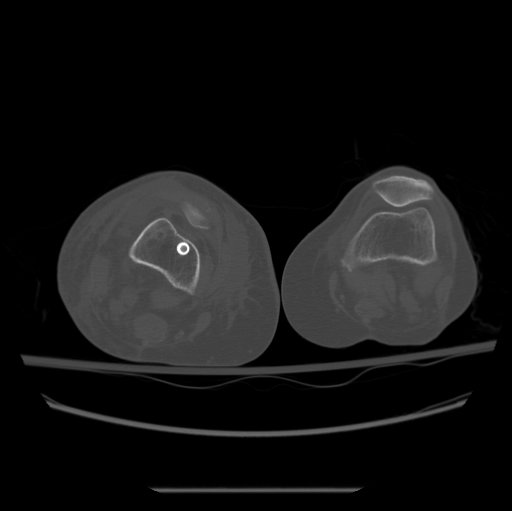

Diagnosis

B. CT

- axial cuts of the femoral neck and the femoral condyles